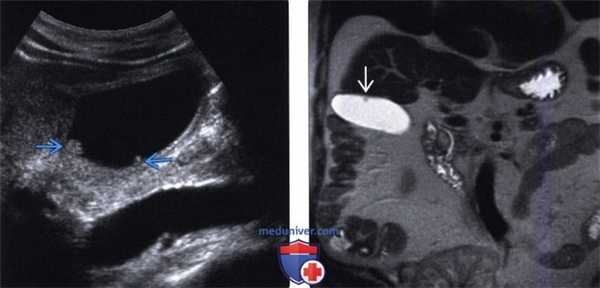

(Левый) На продольном УЗ срезе определяются два мелких холестериновых полипа . Образования неподвижны и не отбрасывают тени.

(Правый) МРТ в режиме Т2 HASTE по поводу объемного образования почки. На корональной томограмме случайно обнаружен мелкий низкоинтенсивный полип, стенка желчного пузыря не изменена.